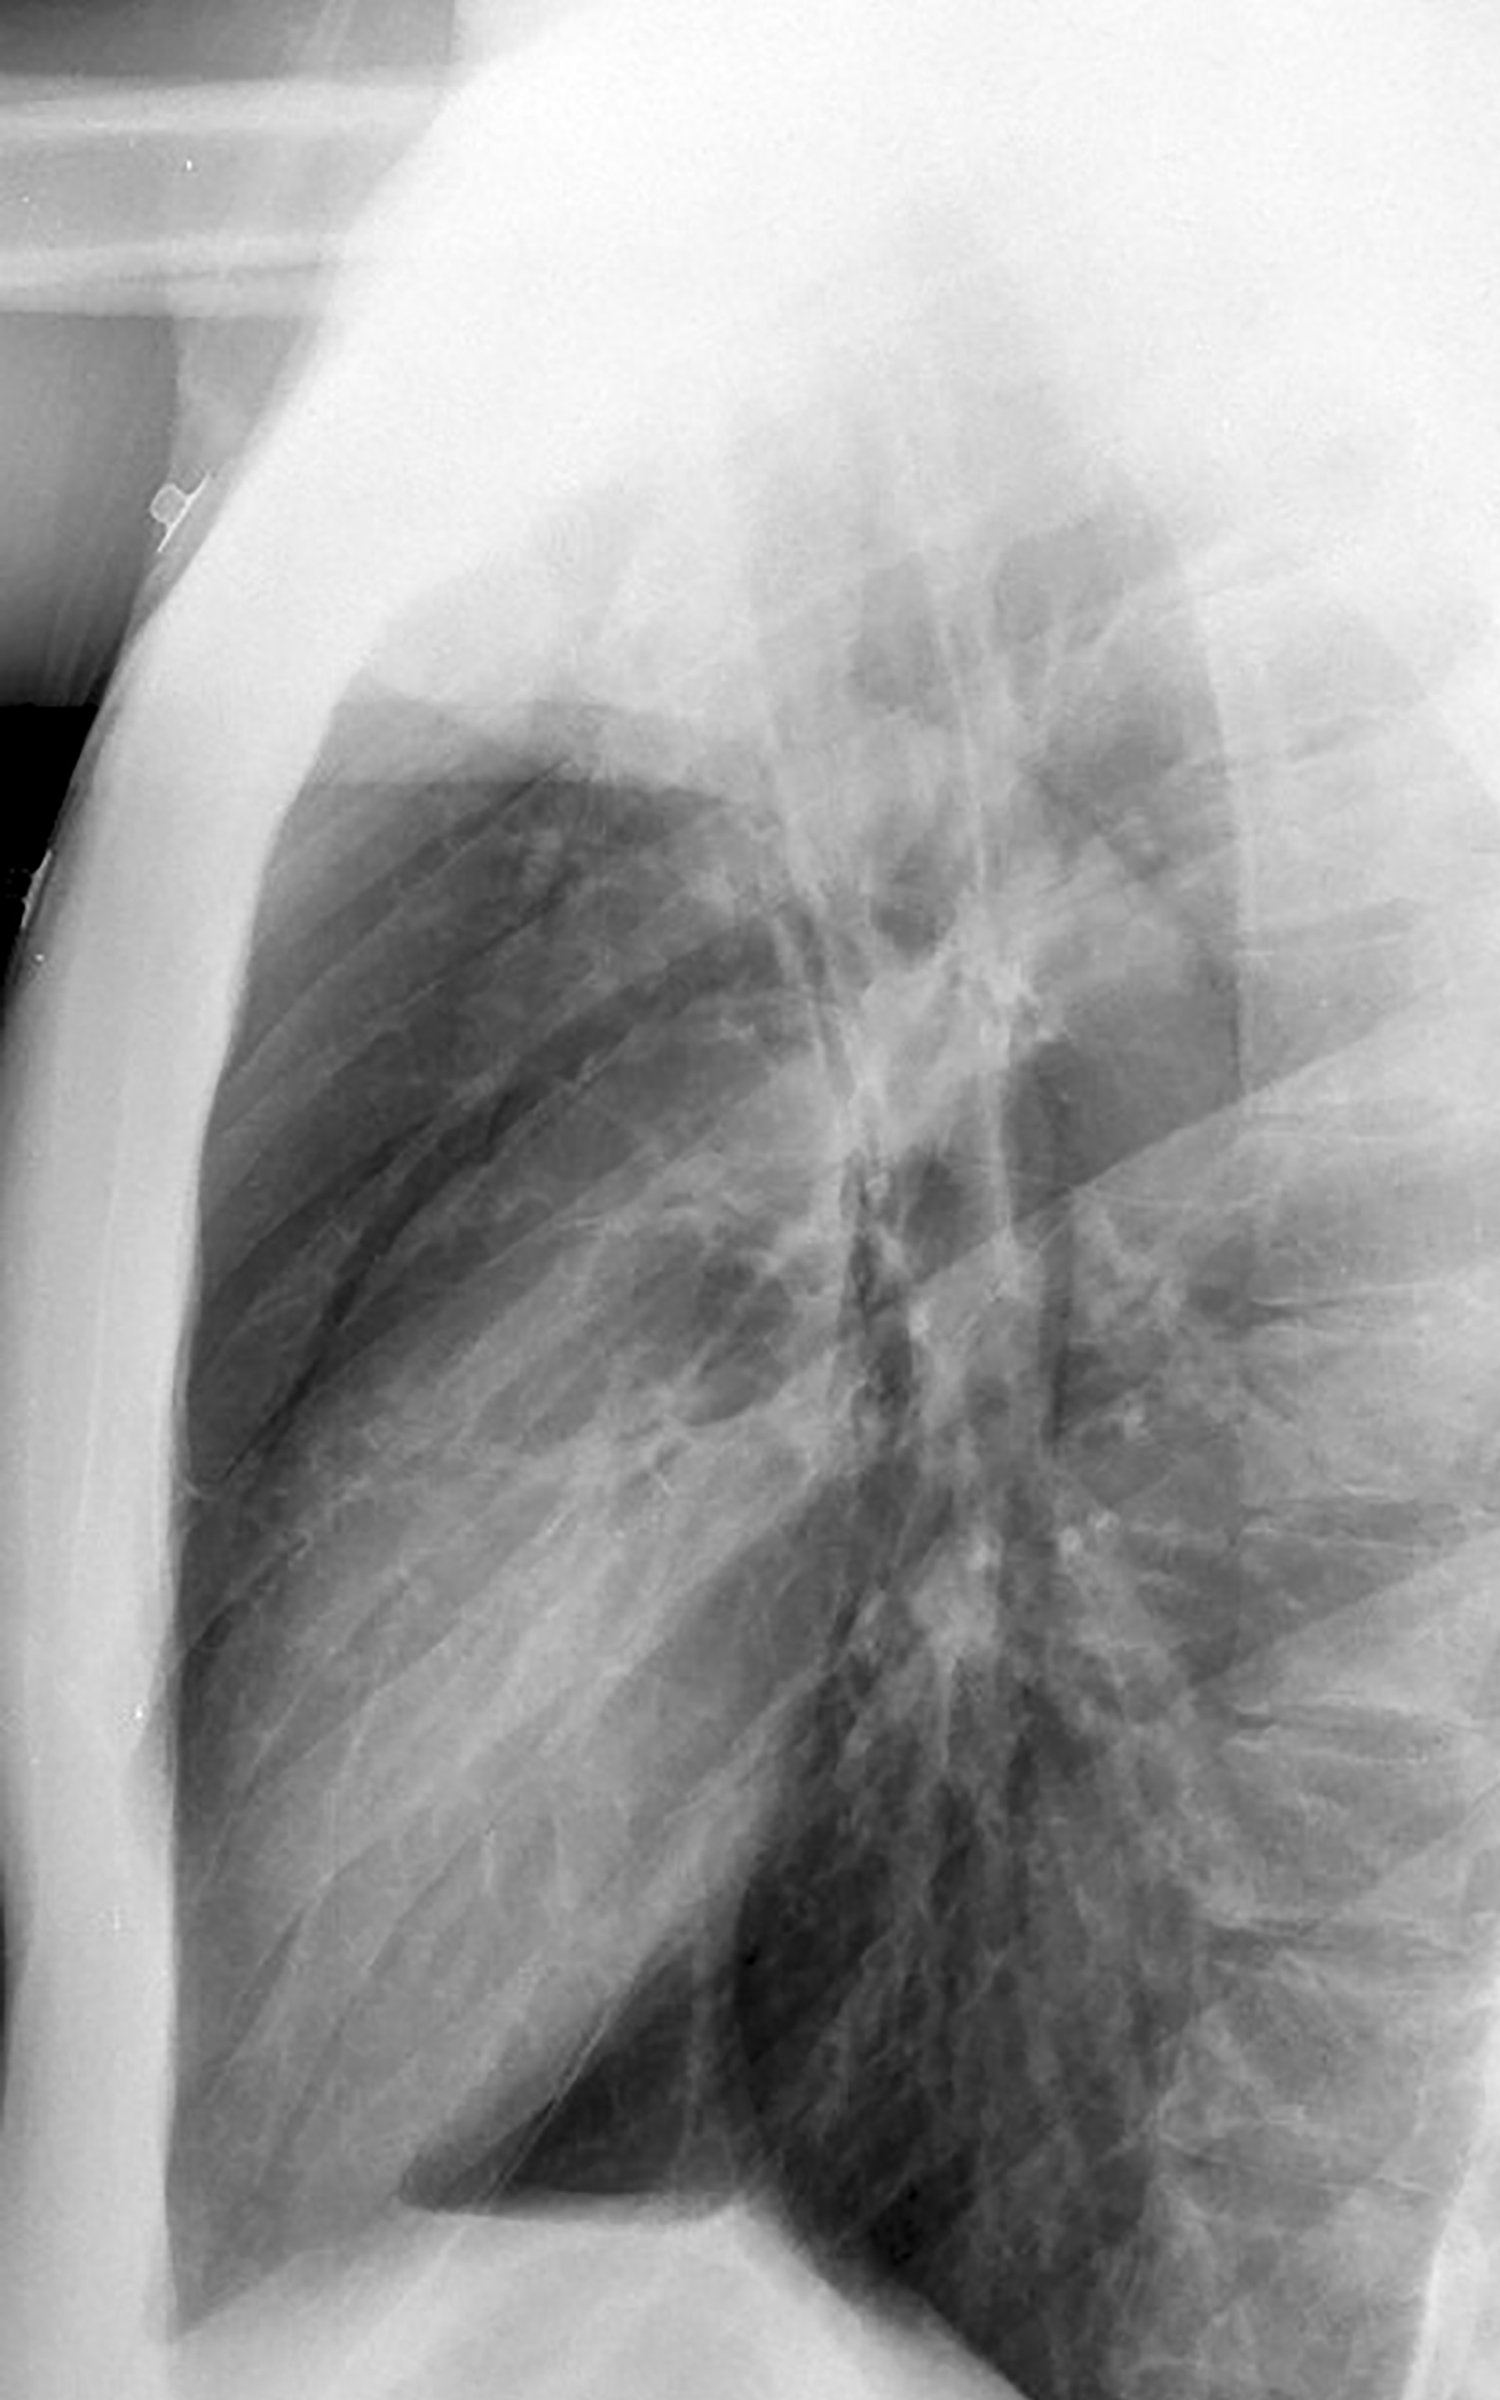

Asthmatic pneumomediastinum lat

Asthma PnMed lat